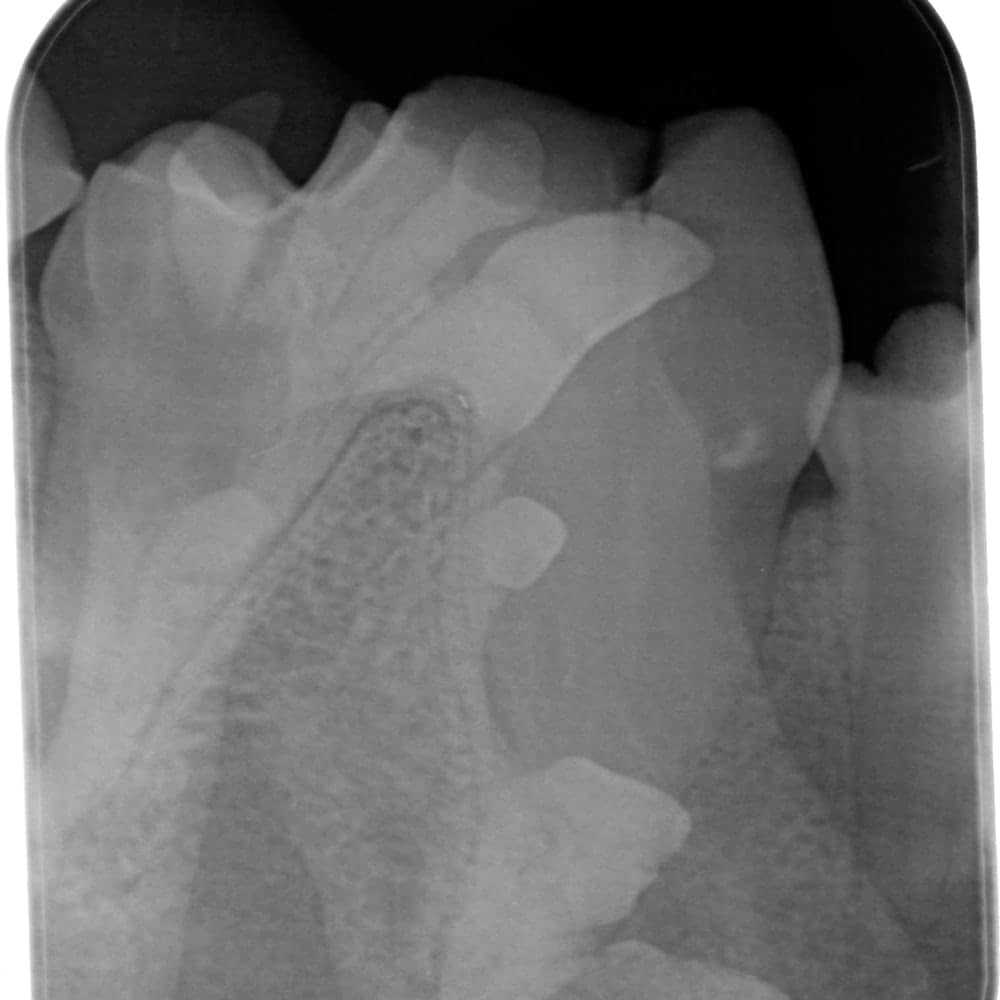

CR (Computed Radiography): The Indirect System

Indirect systems (indirect digital, computed radiography), or CR, use photostimulable phosphor plates to capture the image. These plates are available in several sizes (0, 1, 2, 3, 4, 5) and are about the thickness of a playing card.

These plates must be placed in protective plastic sleeves. Manufacturers recommend using a new sleeve for each EXPOSURE, although they can be reused a few times. Some brands of sleeves need to be torn in the center to be developed, making them unusable a second time. Although phosphor plates are less expensive than digital sensors (about $150 for a size 2 plate and $600 for a size 4), the cost of the sleeves must be considered. They can cost around $1 each, which increases operating expenses. On the other hand, it is less problematic if a patient bites the plate due to its more affordable price.

Phosphor plates can scratch more easily and delaminate if not cleaned with 99% alcohol. They must therefore be replaced after a few years, unlike digital sensors. The variety of sizes offered by this system is its main advantage: size 0 plates easily fit into the mouth of a 1 kg patient or a small cat. Size 4 plates are very useful for taking fewer shots on a large dog and provide a better overall view.

Sometimes, size 4 plates are used to X-ray small companion mammals – this type of system could be advantageous if you treat these kinds of patients in your clinic. Size 5 plates are sold by representatives but, in my humble opinion, offer little benefit in veterinary medicine. Two plates of sizes 0, 2, and 4 make a good kit for all patients.